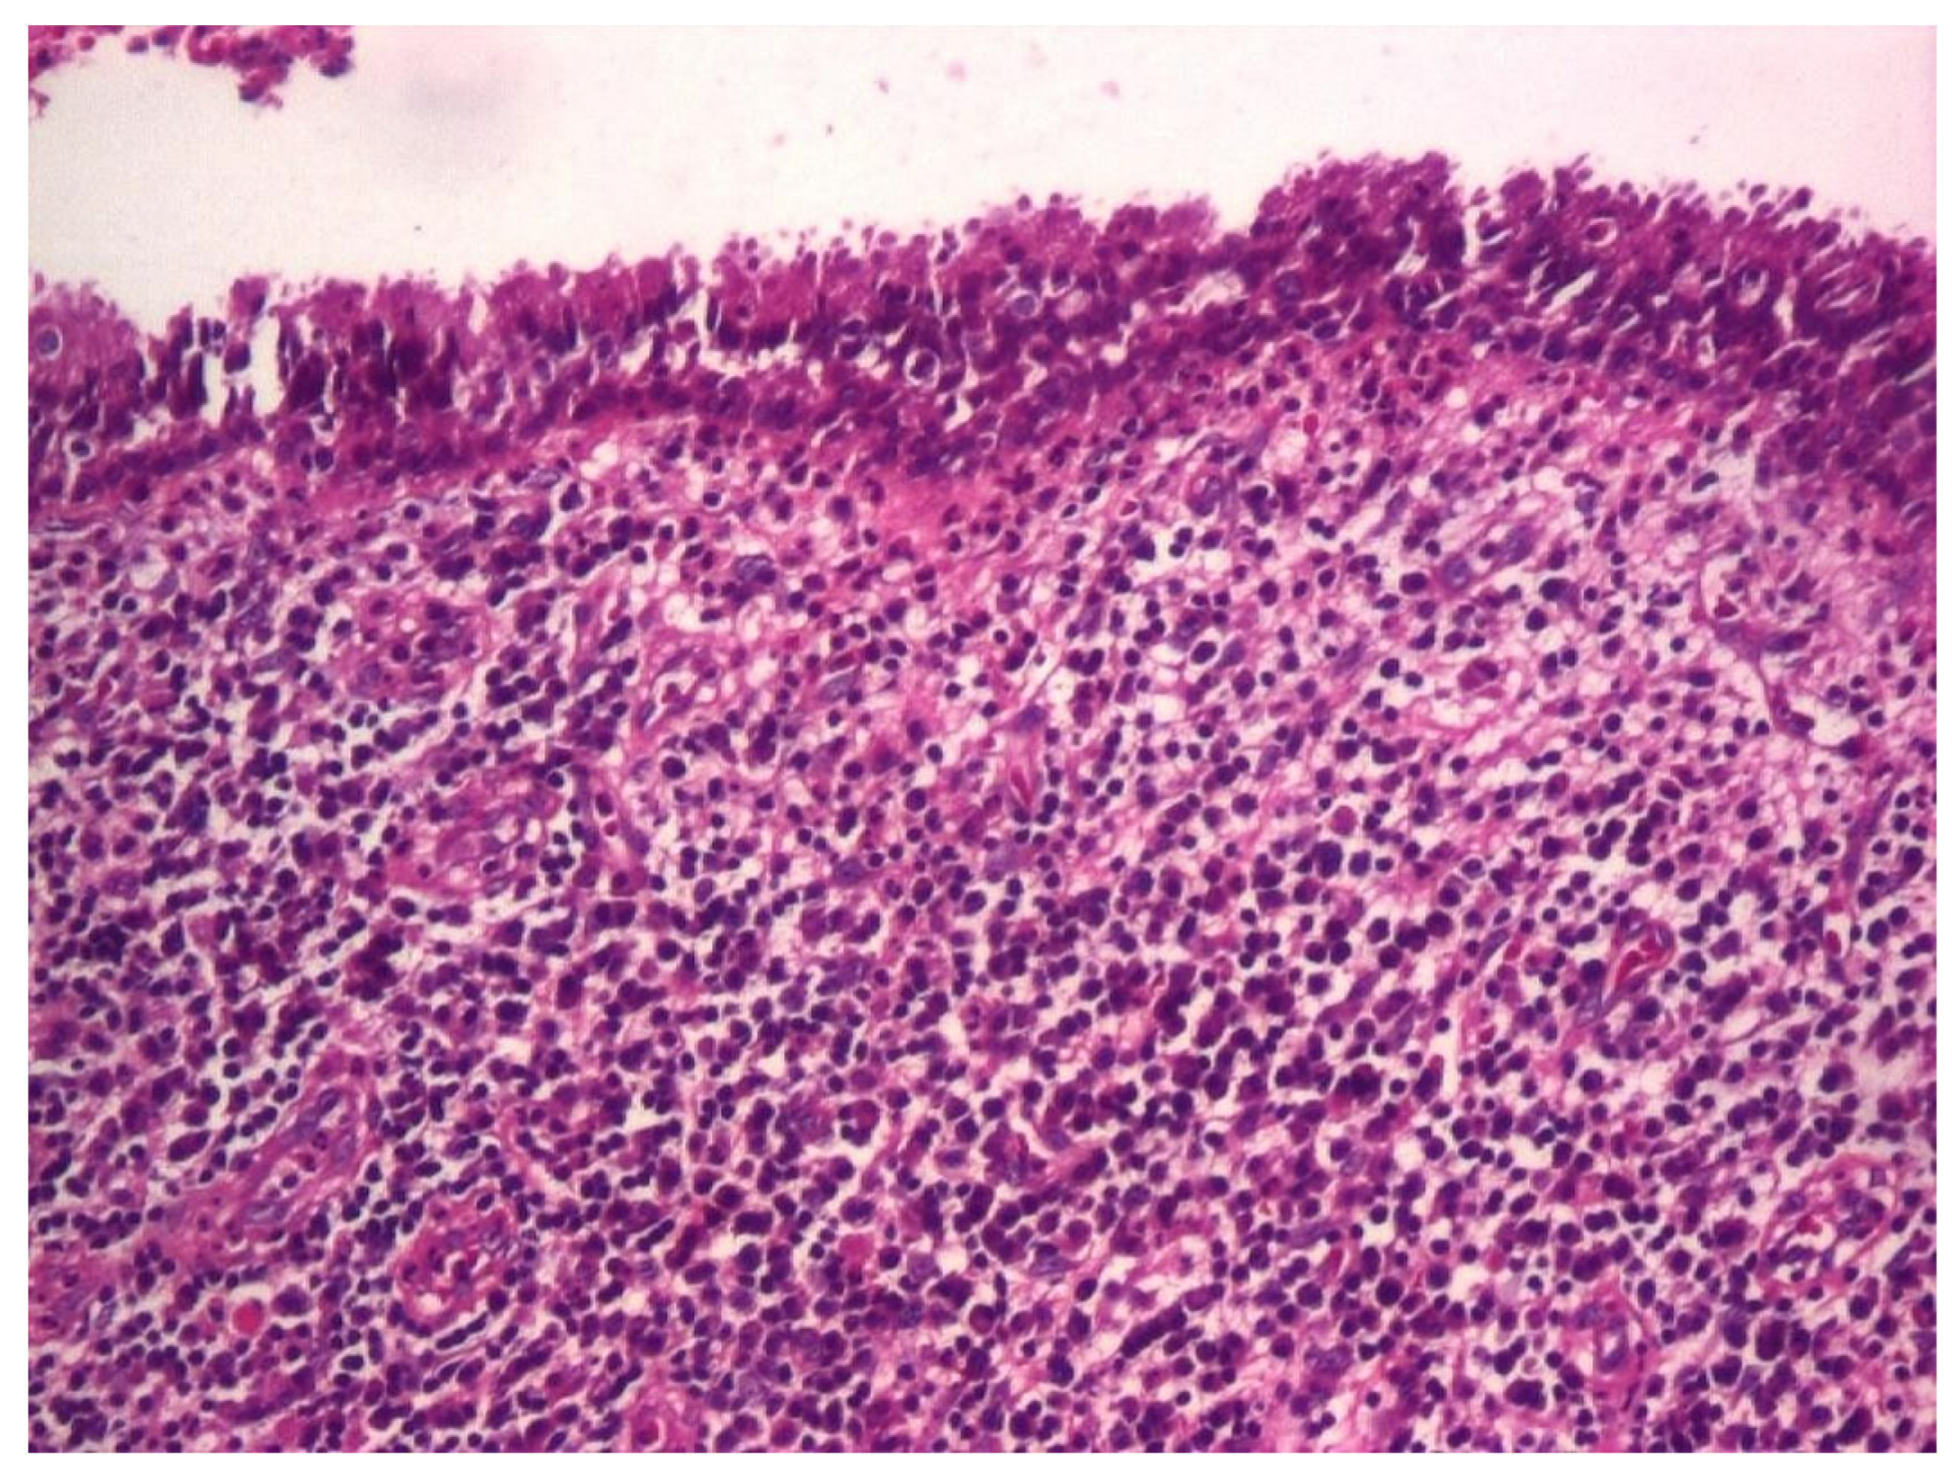

3.1.3. Analysis of Histopathologic and Immunohistochemical Results

| Histopathologic Aspects | Number of Patients |

| Polip | 180 |

| Tympanic membrane mucosa chamber, epithelium with apocrine-like cells, and chronic inflammatory infiltrate | 128 |

| Cell Types | Percentage |

|---|---|

| Lymphocytes T | 42.55% |

| Lymphocytes B | 31.45% |

| Macrophages | 26.00% |